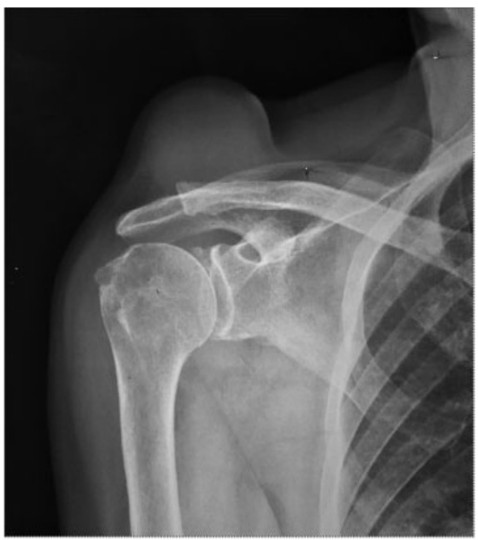

Presentamos dos casos a los que se les realizó una resonancia magnética (RM) con diagnóstico probable de quiste acromioclavicular. El primero, se trataba de una paciente de 77 años del sexo femenino, con una tumoración de hombro derecho, indolora, de un año de evolución. La radiografia mostró una tumoración de partes blandas, superior a la articulación acromioclavicular (AC), bien delimitada, sin lesiones óseas (Fig. 1). La RM mostró una formación quística, superior y en contacto con la articulación AC, sin realce con el contraste, de 86 mm de diámetro, bien delimitada, hiperintensa en secuencias ponderadas en T1 (alto contenido proteico) e hiperintensa en densidad protónica con saturación grasa (DPFS). Ademas, se observó una rotura completa del tendón del supraespinoso (Fig. 2).

Radiografía de frente en rotación externa de hombro derecho. Opacidad nodular en partes blandas por encima de la articulación acromioclavicular (AC).